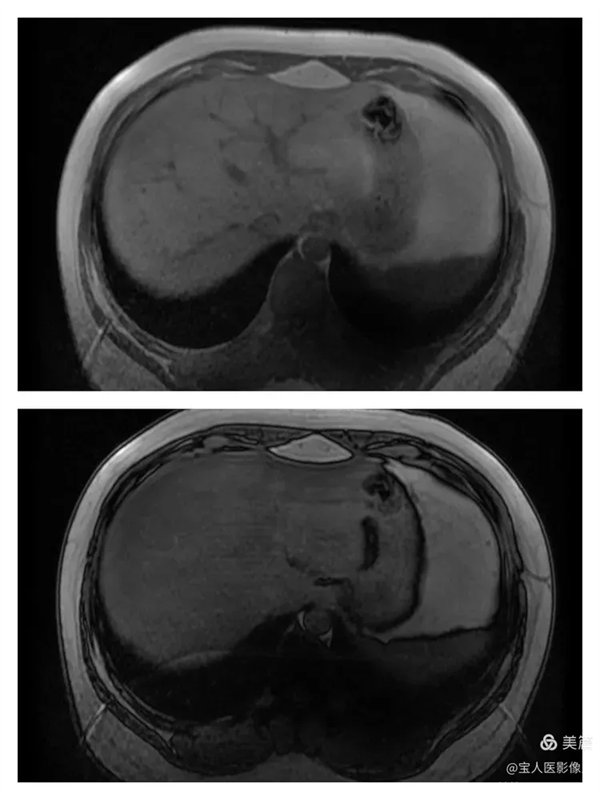

图2

T2WI冠位,轴位,肝实质信号略增高,而脾脏信号正常。